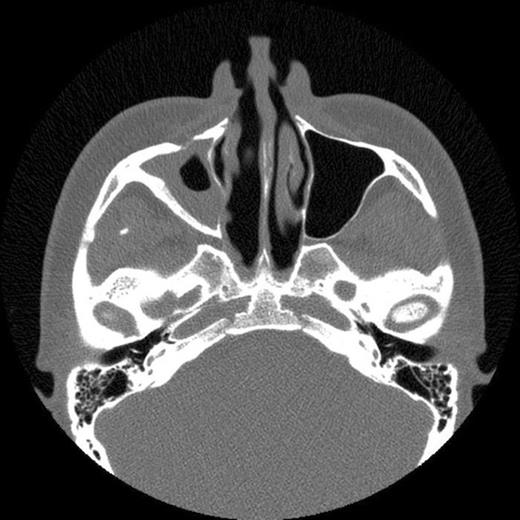

The patient then attended our clinic. Clinical examination and subsequent naso-endoscopy showed evidence of a right sided nasal obstruction with polypoidal mass within the nasal cavity. The patient underwent CT scan sinuses, which showed a well demarcated air defect in the extensively thickened sinus mucosa with large polypoidal mass. Evidence of entry of the cue was seen as a defect in the anterolateral wall of the right maxillary sinus and absent upper medial wall. No FB was seen.

CT scan showing extensive polyp mass in right maxillary sinus with extension into right nasal cavity

The history and CT scan results suggest that following penetration of the snooker cue into the gingivo-labial sulcus it had broken through the right anterolateral maxillary wall and upper medial wall. On withdrawal of the snooker cue, the cue tip had broken off in the maxillary sinus. The FB had then caused localised inflammation resulting in episodes of sinusitis and facial pain. The FB had subsequently been discharged during a coughing episode 12 years later.